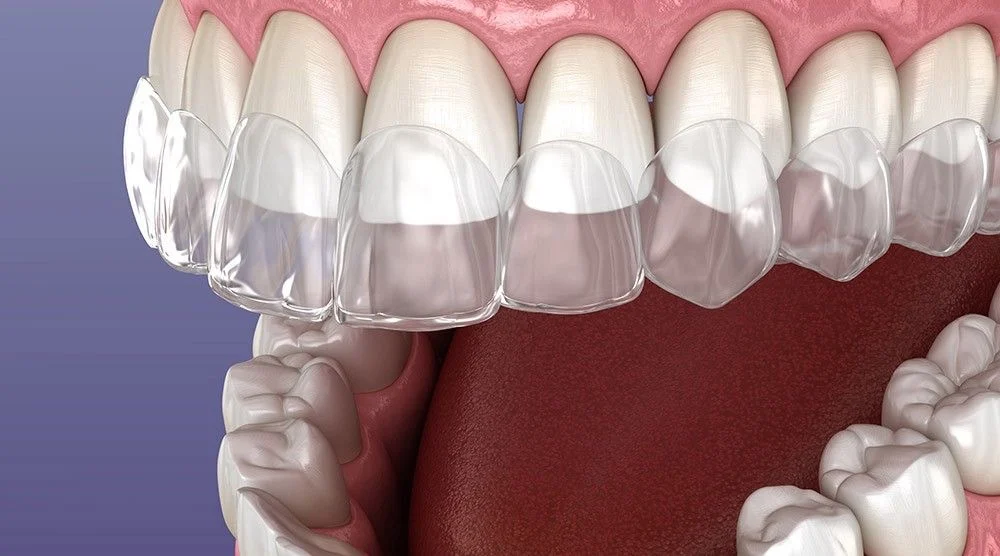

Viniri

Nadoknade se postavljaju samo na prednje površine zuba pri čemu se znatno štedi zubna masa, a postiže se fantastičan estetski efekat.

Viniri

Viniri su zubne nadoknade od kompozita ili keramike koje se postavlaju na intaktne ili minimalno preparisane prednje površine zuba u zavisnosti od slučaja i indikacije.